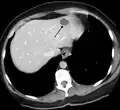

A liver hemangioma as seen on CT

Infantile haemangiomas in the liver are found in 16% of all liver haemangiomas. Its sizes are usually less than 1 to 2 cm in diameter. It may show a "flash-filling" phenomenon in which there is the fast enhancement of the contrast material in the lesion instead of slow, centripetal, nodular filling of the lesions in usual hemangiomas. On CT and MRI, it shows rapid filling during arterial phase, with contrast retention in venous and delayed phases.[38]